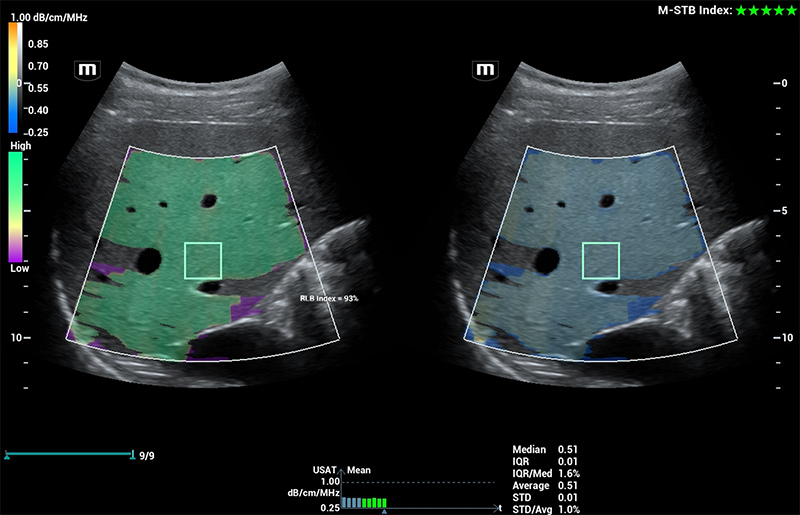

Powered by ZST +

The ZST + platform represents an extraordinary leap forward in ultrasound technology, moving away from traditional beam-forming to channel data processing. This groundbreaking innovation overcomes the traditional trade-offs among spatial resolution, temporal resolution, and tissue uniformity, resulting in unparalleled image quality that empowers infinite imaging solutions.

Resona I9 provides comprehensive clinical solutions for dedicated applications. Based on in-depth insights into different clinical scenarios, it delivers innovations that give users extreme clarity, outstanding intelligence and enhanced diagnostic confidence.